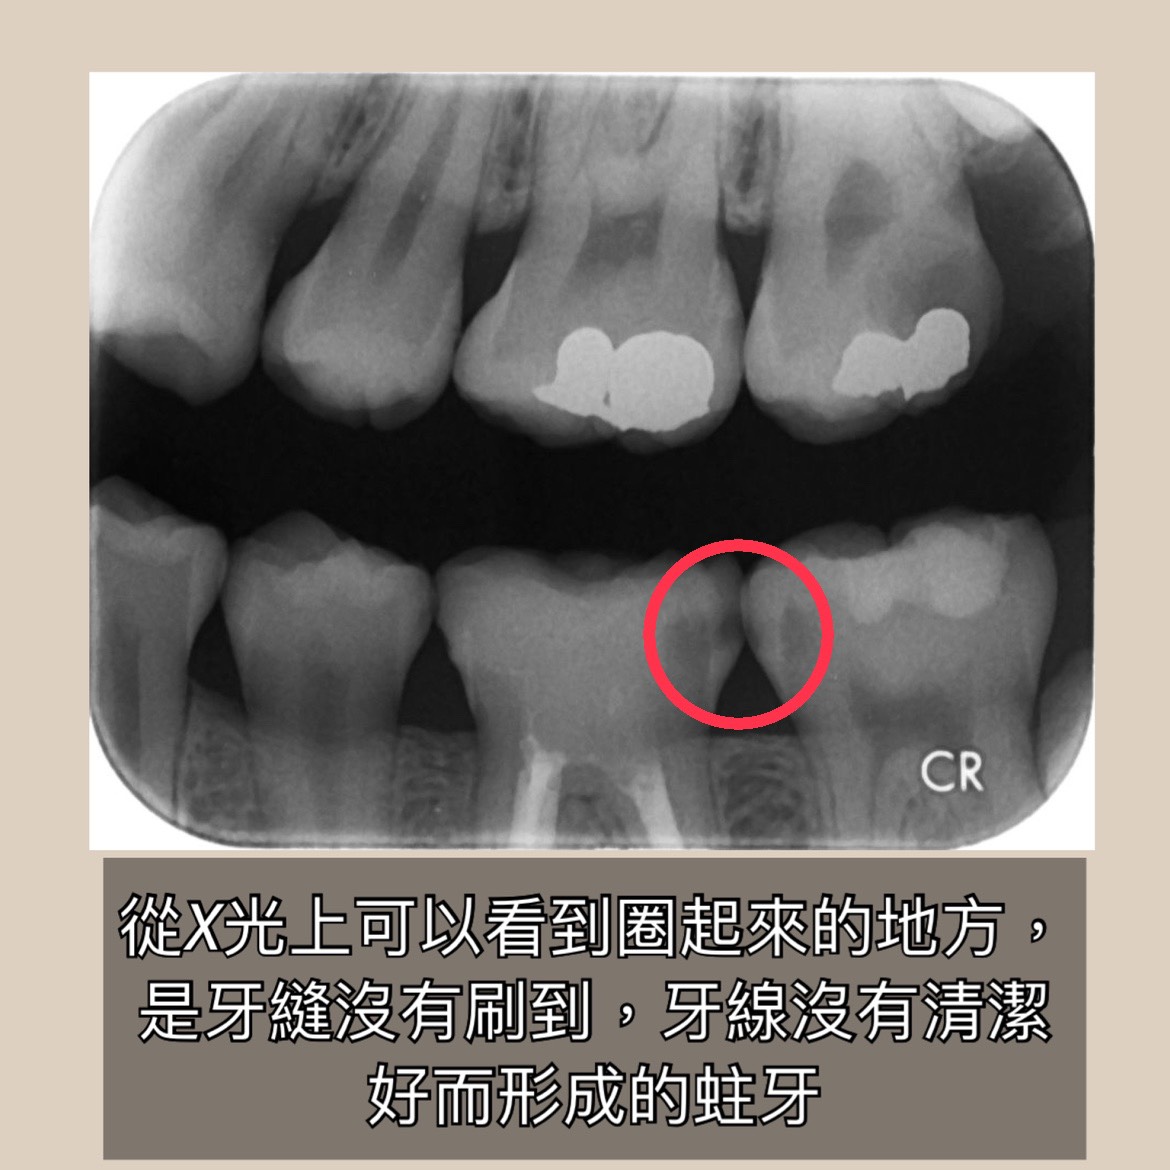

刷牙每日至少兩次,每次至少兩分鐘,最重要的是睡前絕對要記得刷牙(可以使用含氟牙膏哦!),像有些牙縫容易卡住的,就需配合牙線做清潔✨